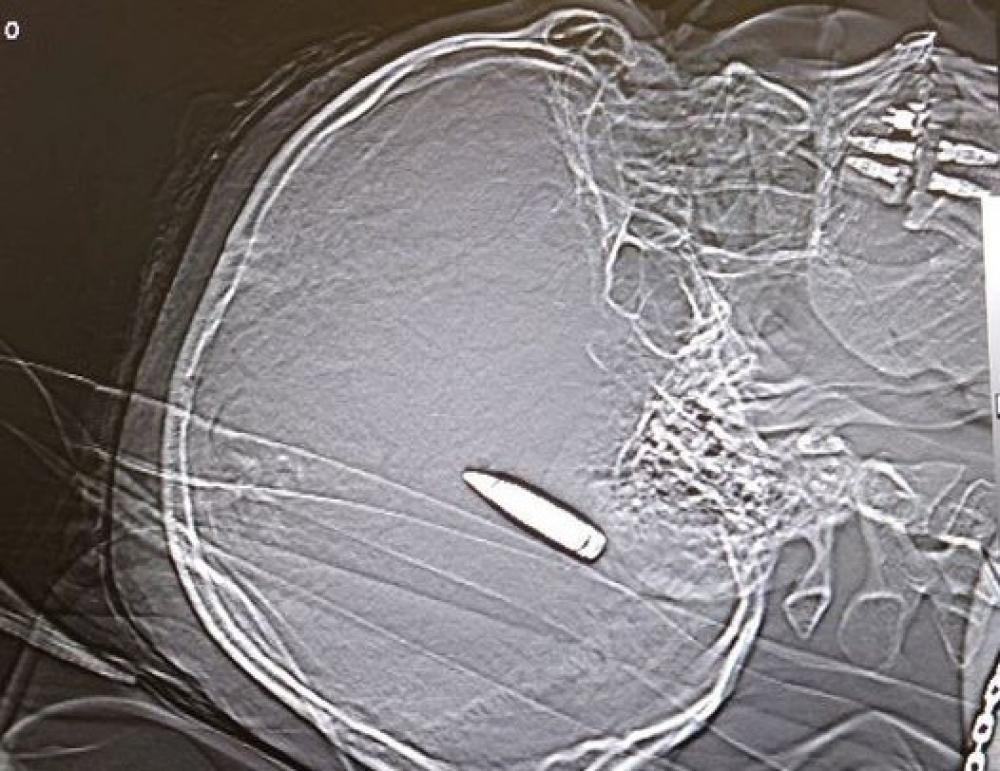

Куля посередині мозку: у Дніпрі лікарям дивом вдалося відновити стабільність стану солдата

У лікарні Дніпра рятують пацієнта з кулею посередині мозку. Таке поранення вважається смертельним, але медики роблять все можливе, аби врятувати життя 35-річному пацієнту.

За словами Сергія Риженка, куля розламала праву тім'яну ділянку черепа і разом з кістковими відламками зайшла в центр мозку.

"Величезний крововилив в рановий канал. Четверту годину під мікроскопом усі: нейрохірурги, анестезіологи, медсестри - рятують життя 35-річного українця Олександра",  - додав лікар.